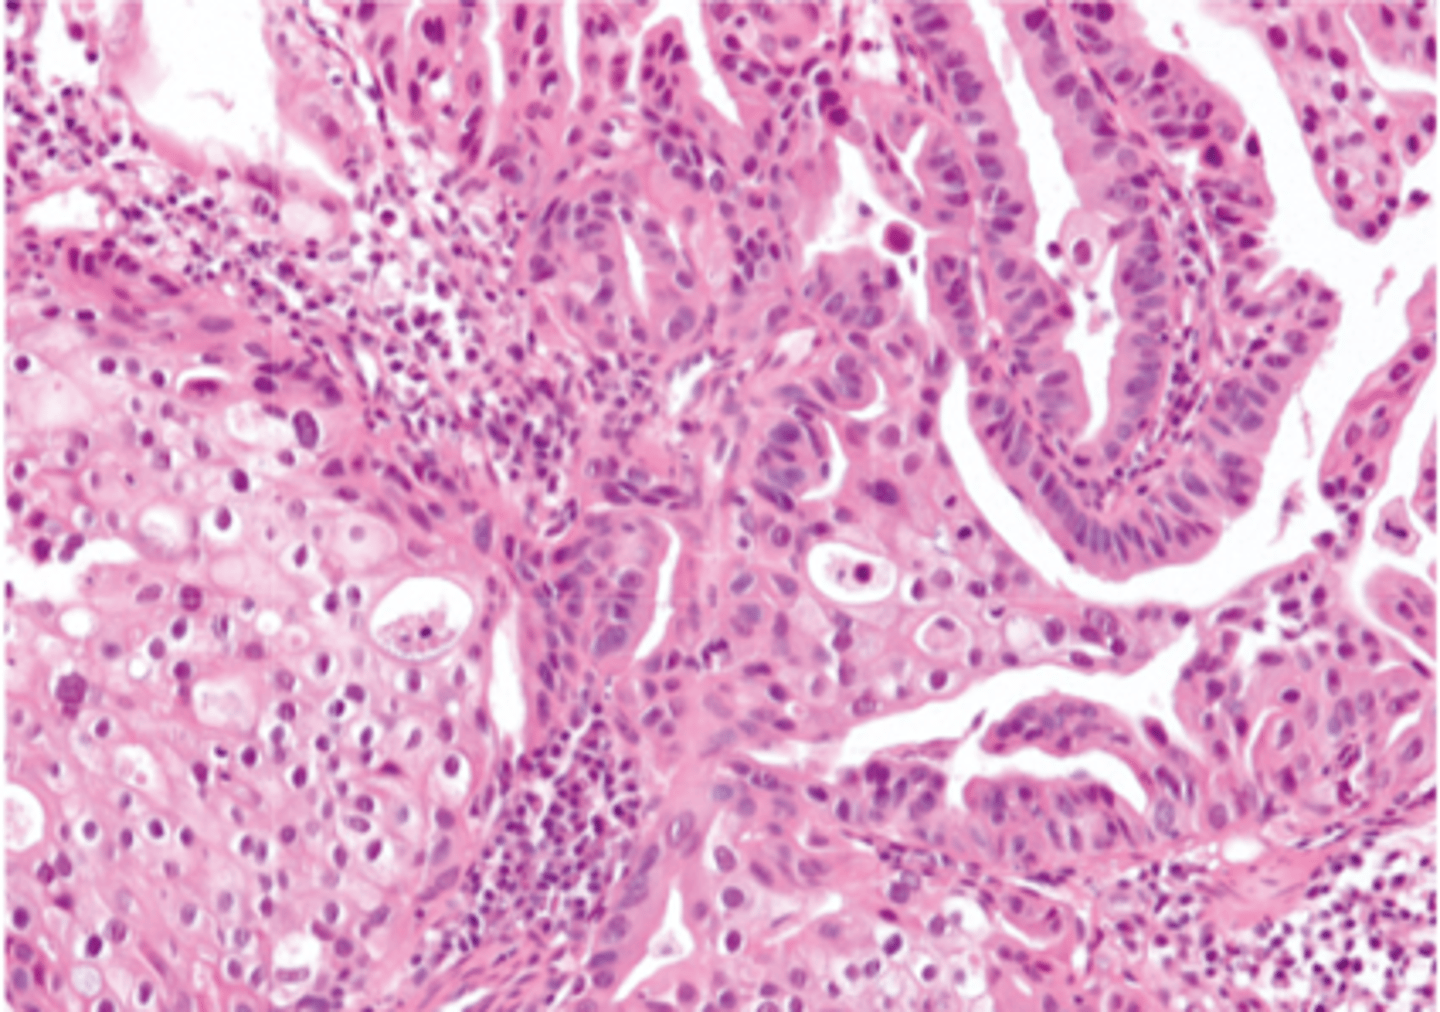

Describe the histological appearance of prostatic hyperplasia

- Hyperplasia and papillary proliferation of the glandular tissue

- Stromal hyperplasia

without infiltration of surrounding tissues

describe the histological appearance of prostatitis

Glands dilated

Necrotic neutrophils and sloughed epithelial cells